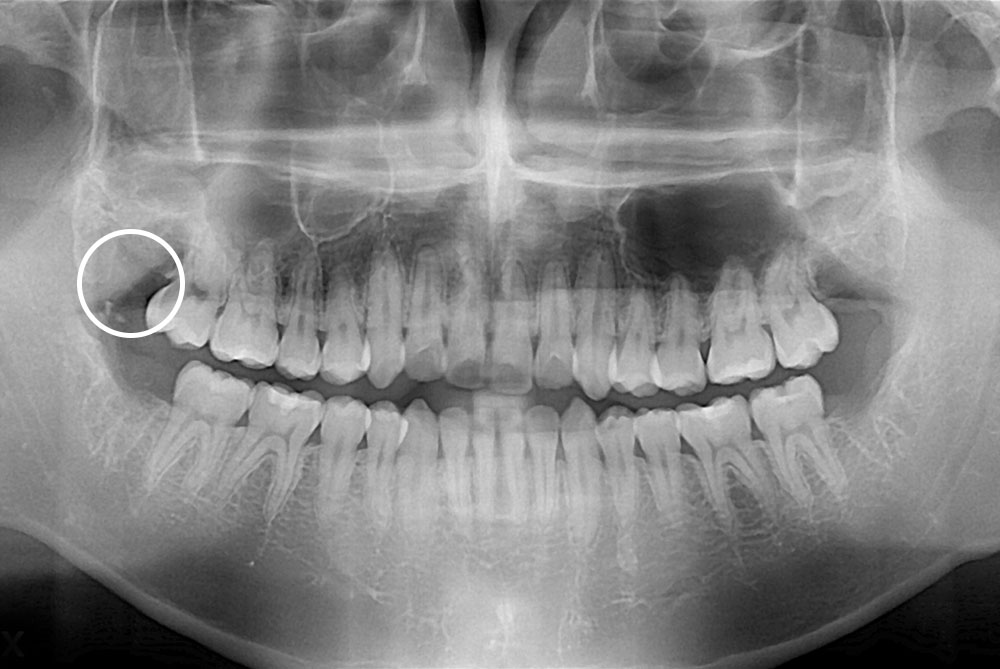

[사랑니] 매복 사랑니 발치

치료전 : 2019-01-23